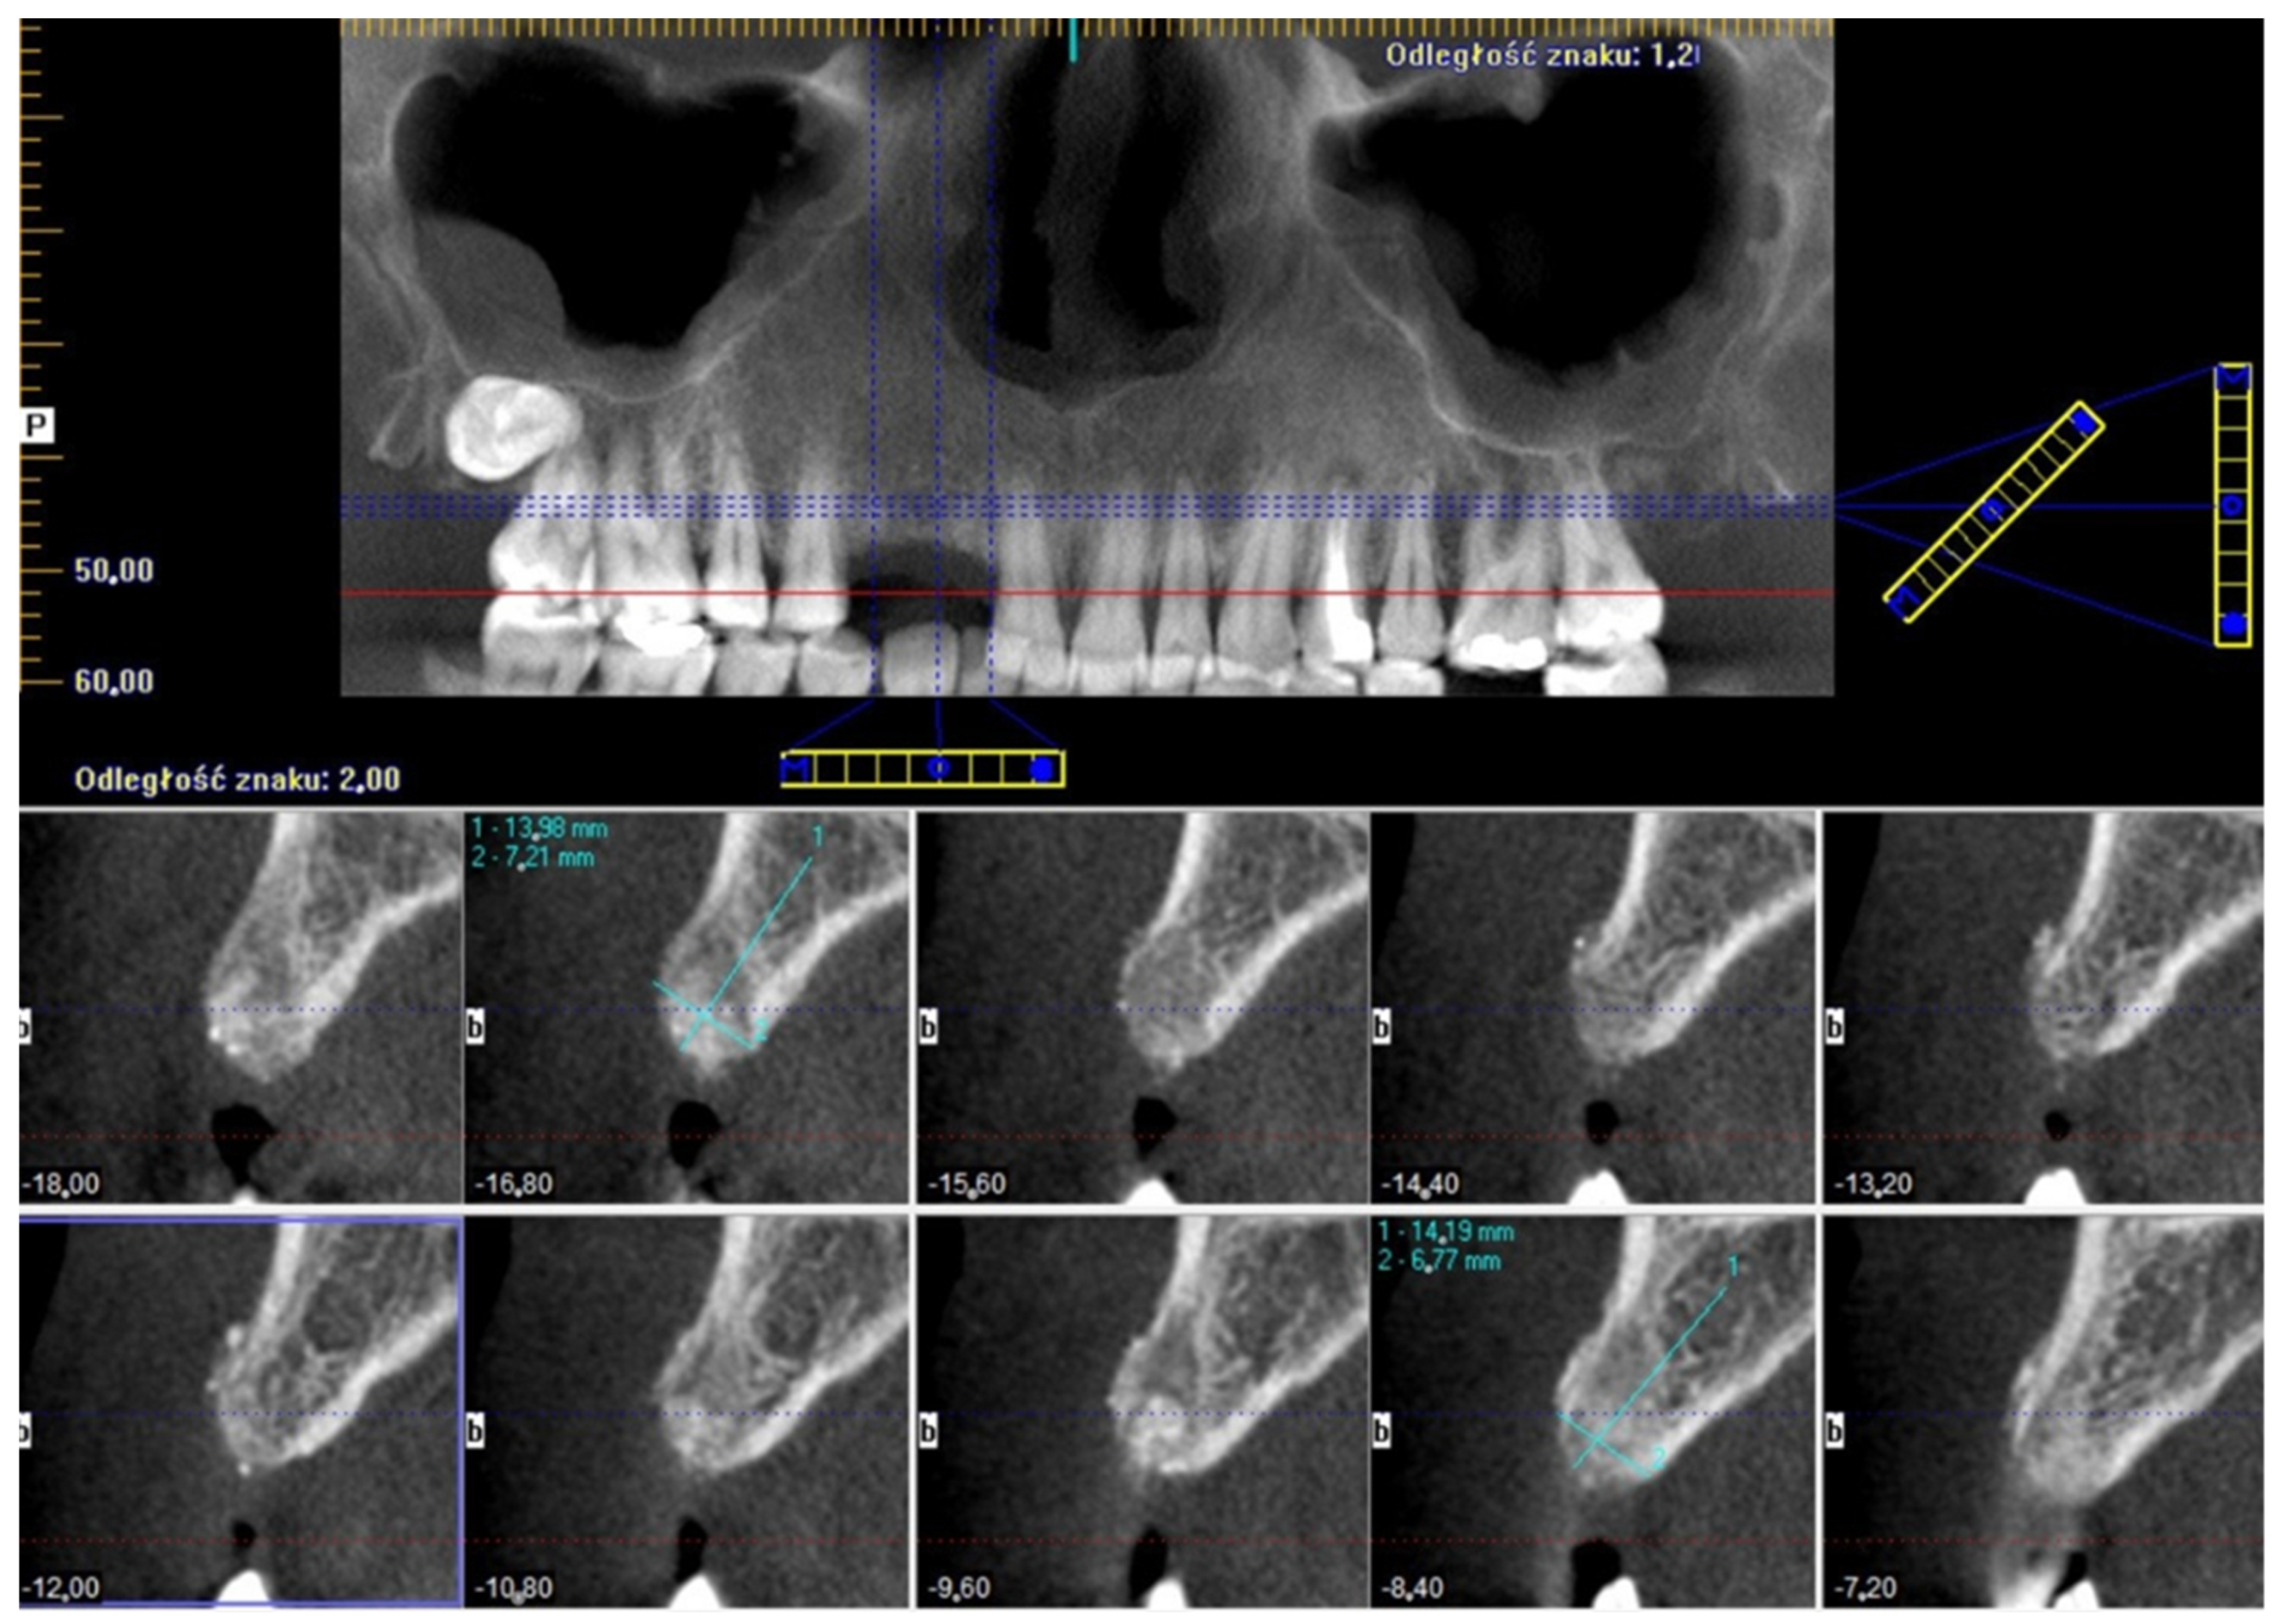

3.2. Surgery